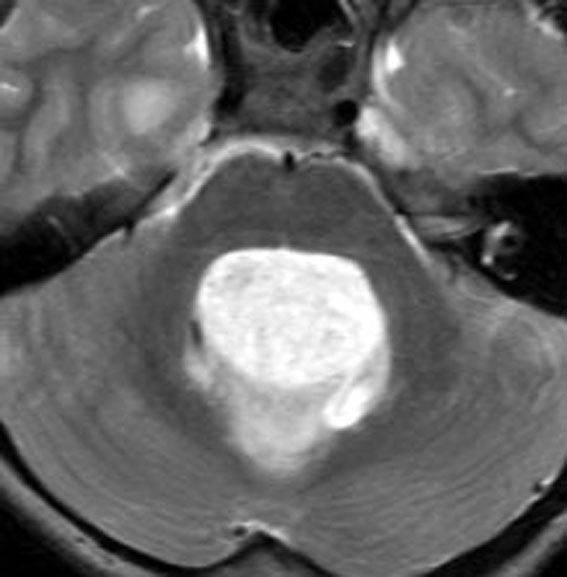

第4脳室腫瘍のMRI像

左は脳幹部腫瘍(退形成性神経節膠腫),右は小脳腫瘍(毛様細胞性星細胞腫)です。どちらも第4脳室を埋め尽くすように発育しています。これらはどちら側から発生したかが明瞭な例ですが,第4脳室腫瘍の中には脳幹部からか小脳からか解らないものもあります。でも多くは小脳側からです。脳幹部側からで注意しなければならないのは上衣腫と血管芽腫です。